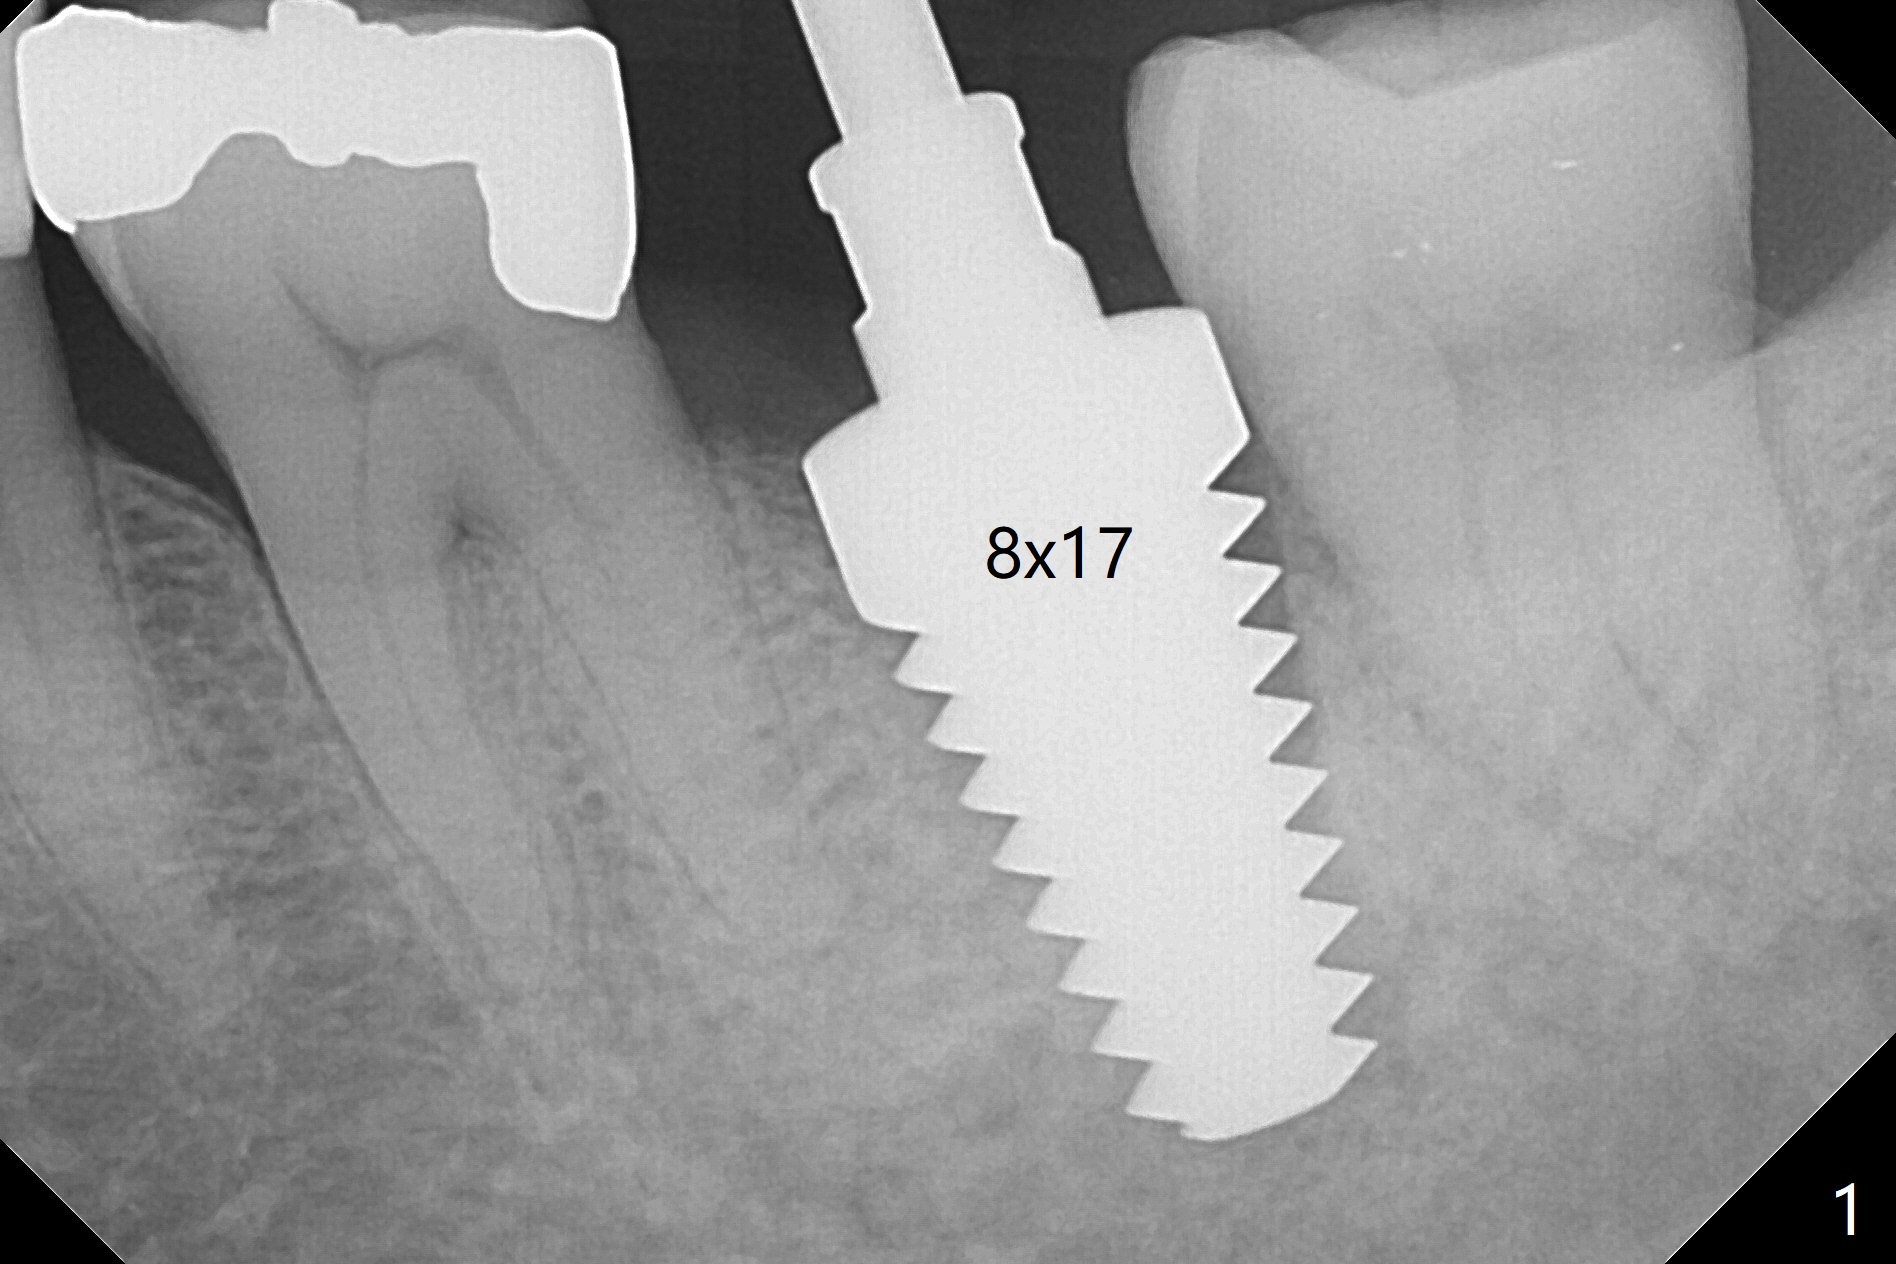

When the mobile tooth #18 with apical granulation tissue is extracted, the socket is large and long (close to the Inferior Alveolar Canal (Fig.2,3 red dashed line). Without drilling, a 7 mm bone level tap does not obtain stability. A 8x17 mm tapered tap reaches the bottom of the socket with minimal stability, but coronally it is close to the tooth #32 (Fig.1). When a 7x14 mm cylindrical tap is placed, it is shy of the bottom of the socket (Fig.2 *), but the trajectory improves. A 7x14 mm tissue-level implant is placed with ~45 Ncm (still not secure) with Vanilla graft placed mainly distolingually (Fig.3). With the large implant, the socket is closed 8 days postop (Fig.4). The soft and hard tissues appear to heal 3 months postop (Fig.5,6). A healing abutment (Fig.7 H) is placed to push the mesial papilla mesially (*). Two weeks later impression is taken with ease because of the healing abutment. There is no bone loss 4.5 months postop (immediately post cementation, Fig.8).